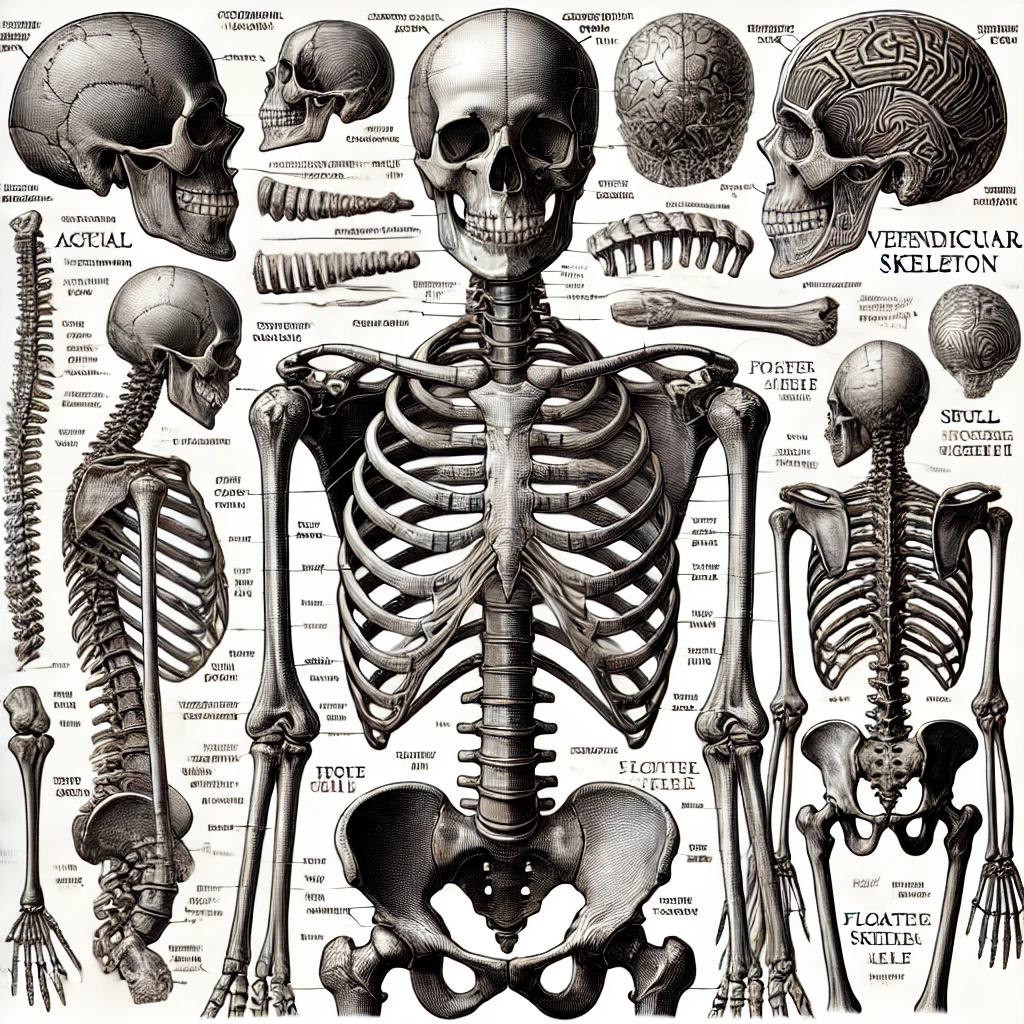

골격(Skeleton)관련 해부학 용어 정리

1. 전체 골격(Skeletal system)

- 골격: 뼈대, Skeleton(스켈러튼)

- 뼈: Bone(본)

- 연골: Cartilage (카(r)터리지)

- 관절: Joint (조인트)

- 인대: Ligament (리거먼트)

- 힘줄: Tendon (텐던)

- 골막: Periosteum (페리오스티엄)

- 골수: Bone marrow (본 매로우)

- 골단판: 성장판, Epiphyseal plate (에피피지얼 플레이트)

2. 골격의 구분

- 축골격: 몸통뼈대, Axial skeleton (액시얼 스켈러튼)

- 부속골격: 팔다리뼈대, Appendicular skeleton (어펜디큘러 스켈러튼)

3. 두개골 (Cranial and Facial Bones)

- 두개골: 머리뼈, Skull (스컬) or Cranium (크레이니엄)

- 얼굴뼈: Facial bones (페이셜 본즈)

- 전두골: 이마뼈, Frontal bone (프런틀 본)

- 두정골: 마루뼈, Parietal bone (퍼라이어틀 본)

- 측두골: 관자뼈, Temporal bone (템퍼럴 본)

- 후두골: 뒤통수뼈, Occipital bone (옥시피틀 본)

- 접형골: 나비뼈, Sphenoid bone (스피노이드 본)

- 사골: 벌집뼈, Ethmoid bone (에쓰모이드 본)

- 상악골: 위턱뼈, Maxilla (맥실러)

- 하악골: 아래턱뼈, Mandible (맨더블)

- 광대뼈: 관골, Zygomatic bone (자이고매틱 본)

- 코뼈: 비골, Nasal bone (네이즐 본)

4. 척추 (Vertebral Column)

- 척추: Vertebral column (버터브럴 컬럼)

- 경추: 목뼈, Cervical vertebrae (서비컬 버터브레이)

환추: 제1경추, Atlas (애틀러스)

축추: 제2경추, Axis (액시스)

- 흉추: 등뼈, Thoracic vertebrae (쏘래식 버터브레이)

- 요추: 허리뼈, Lumbar vertebrae (럼바 버터브레이)

- 천골: 엉치뼈, Sacrum (세이크럼)

- 미골: 꼬리뼈, Coccyx (칵식스)

5. 가슴우리 (Thoracic Cage)

- 갈비뼈: 늑골, Ribs (립즈)

- 진늑골: 참갈비뼈, True ribs (트루 립즈)

- 거짓갈비뼈: 가성 늑골, False ribs (폴스 립즈)

- 뜬갈비뼈: 부유 늑골, Floating ribs (플로팅 립즈)

- 흉골: 복장뼈, Sternum (스터넘)

병형돌기: 칼돌기, Xiphoid process (자이포이드 프로세스)

6. 팔뼈, 상지뼈 (Upper Limb Bones)

- 빗장뼈: 쇄골, Clavicle (클래비클)

- 어깨뼈: 견갑골, Scapula (스캐퓰러)

- 위팔뼈: 상완골, Humerus (휴머러스)

- 노뼈: 요골, Radius (레이디어스)

- 자뼈: 척골, Ulna (얼너)

- 손목뼈: 수근골, Carpal bones (카펄 본즈)

- 손허리뼈: 중수골, Metacarpal bones (메타카펄 본즈)

- 손가락뼈: 지절골, Phalanges (패랜지즈)

7. 다리뼈, 하지 뼈(Lower Limb Bones)

- 볼기뼈: 관골 또는 골반뼈, Pelvic bone (펠빅 본)

- 넙다리뼈: 대퇴골, Femur (피머)

- 무릎뼈: 슬개골, Patella (퍼텔러)

- 정강이뼈: 경골, Tibia (티비아)

- 종아리뼈: 비골, Fibula (피뷸러)

- 발목뼈: 족근골, Tarsal bones (타설 본즈)

- 발허리뼈: 중족골, Metatarsal bones (메타타설 본즈)

- 발가락뼈: 지절골, Phalanges (패랜지즈)